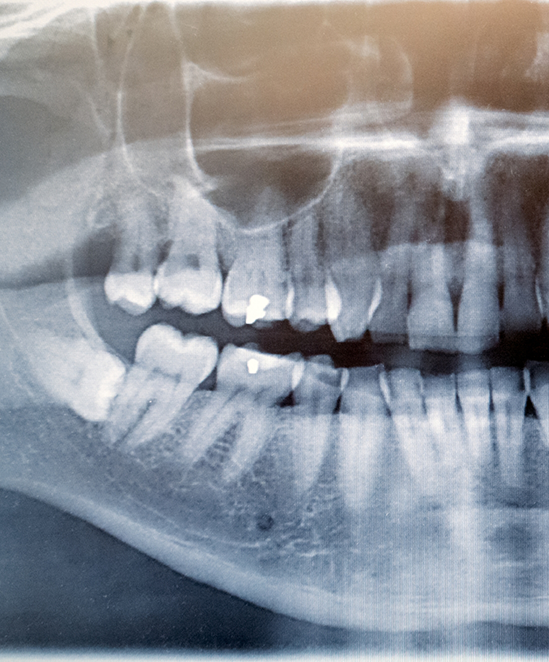

Wisdom teeth, also called the third molars, are the last set of teeth to erupt at the back of the mouth, and they often make their appearance during the teenage years or early adulthood. While some lucky individuals have room in their mouth for wisdom teeth (or don’t have them at all), most of us end up needing to have the teeth removed before they begin causing oral health issues. Luckily, the wisdom tooth extraction process is incredibly straightforward and something our team is happy to guide you or a family member through. To get started, contact our Encinitas dental office!

The wisdom tooth extraction process is relatively straightforward, even when multiple wisdom teeth need to be extracted. After the mouth is numbed (sedation dentistry is also often used), if the teeth have emerged above the gumline, they can be carefully removed with special forceps. If they’re still beneath the gums, small openings can be made to access them, and from there, they’re often removed in small pieces to make things easier. Patients will need to endure a brief healing period following the procedure.